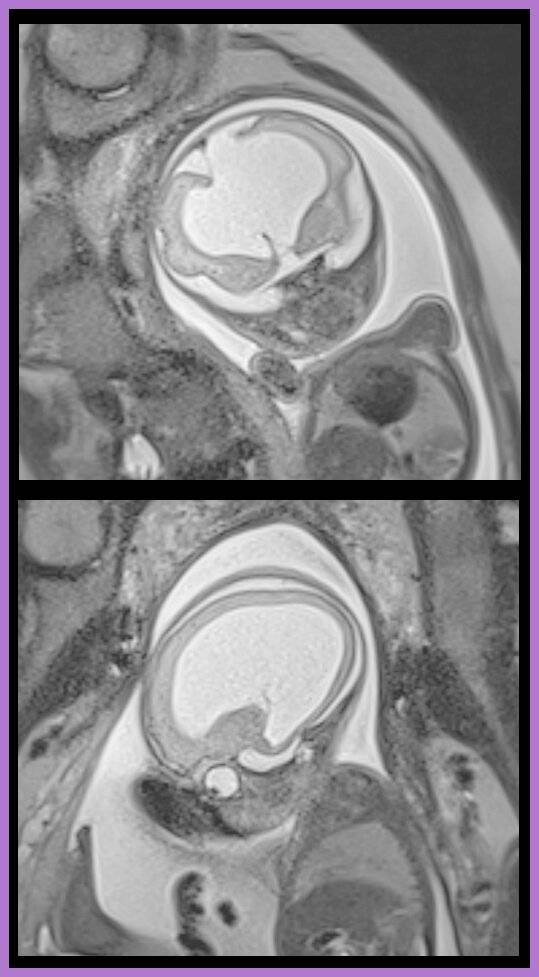

Der Tumor in der Leber, ein Bandscheibenvorfall, eine verkalkte Arterie – drei gänzlich unterschiedliche Diagnosen, bei denen eines gleich ist: Die Radiologen des Elisabeth-Krankenhaus Rheydt sehen nicht nur millimetergenau ins Innere des Körpers der Patienten, sie behandeln ihn dank der Bilder auch mit. So ist es zum Beispiel in der Gefäßmedizin, wenn verstopfte Arterien die Gesundheit des Patienten gefährden. Dank der Gefäßdiagnostik mittels CT oder MRT können die Ärzte die Behandlung planen und dann in der DSA die Katheter, die dafür sorgen, dass das Blut wieder frei zirkuliert, minimalinvasiv einsetzen. Den großen Vorteil gegenüber einer konventionellen Operation erklärt Prof. Dirk Blondin, Chefarzt der Radiologie: „Für den Eingriff reicht eine lokale Betäubung, die Intervention ist für den Patienten gleichzeitig effektiv und schonend.“ Voraussetzung für diese Methode ist die moderne Digitale Subtraktions- Angiografie (DSA) Anlage mit 3D Funktion. Auch komplexe Interventionen bei langstreckigen Verschlüssen der Beinarterien können die Radiologen minimalinvasiv behandeln. Hierbei kommen nicht nur Ballons und Stents, sondern auch Gefäßfräsen zum Einsatz, die ähnlich einem Bohrer die verkalkten Arterien wiedereröffnen. Es braucht nicht nur modernste Technik, sondern auch Ärzte, die innovative Verfahren beherrschen und entsprechend viele Fälle pro Jahr behandeln. Prof. Blondin: „Dank der erfahrenen Oberärzte Bernd Paulußen und Dr. Carsten Starke sind wir bei dieser Methode führend in der Region.“ Das gilt auch für die Behandlung von Tumoren in der Leber. Selbst in fortgeschrittenen Krebsstadien kann die interventionelle Radiologie für bestimmte Patienten Linderung bringen. Operativ nicht entfernbare Lebermetastasen können in der Radiologie durch minimalinvasive interventionelle Methoden wie der Thermoablation oder auch der über die Arterien durchgeführte Chemoembolisation (TACE genannt) zum Stillstand oder zum Rückgang gebracht werden. Dazu wird das Chemotherapeutikum über feinste Katheter direkt am Tumor oder den Metastasen in der Leber eingebracht. Diese Techniken haben sich besonders bei den lebereigenen Tumoren im nicht mehr operablen Stadium bewährt. Für dieses Verfahren erhält Prof. Blondin überregionale Einweisungen. Nicht alle im MRT nachgewiesenen Bandscheibenvorfälle müssen operiert werden. Die konservative Behandlung durch die niedergelassenen neurochirurgischen oder orthopädischen Kollegen kann durch gezielte Schmerzspritzen an den gereizten Nerv direkt an der Wirbelsäule unterstützt werden. Diese Spritzen (PRT genannt) werden punktgenau unter CT-Kontrolle gesetzt. Bei einer Überweisung durch einen Schmerztherapeuten bietet die Radiologie der Städtischen Kliniken diese Mitbehandlung auch für gesetzlich versicherte Patienten an. Besondere Expertise haben die Städtischen Kliniken auch bei kinder-radiologischen Fragestellungen. Dazu bedarf es speziell ausgebildeten Personals. „Denn bei Kindern gibt es eine Reihe von genetisch bedingten Erkrankungen, die bereits früh zu Entwicklungsstörungen führen und bei denen es wichtig ist, diese so schnell wie möglich zu identifizieren“, so der Chefarzt. Da die Säuglinge und Kleinkinder für die Diagnostik im MRT medikamentös beruhigt werden müssen, sind Prof. Blondin und seine leitende Oberärztin Dr. Ira Gabor glücklich, dass die Zusammenarbeit mit der Kinderklinik seit vielen Jahren so exzellent funktioniert. „Wir arbeiten Hand in Hand für die Gesundheit der Kinder“, sagt Prof. Blondin. Eine weitere Spezialuntersuchung der Radiologie sind die sogenannten „Fetalen MRT“ Untersuchungen. Hierbei werden Föten im Mutterleib mit der Kernspintomographie schonend untersucht. Denn seltene angeborene Fehlbildungen und Erkrankungen sollen frühzeitig sicher diagnostiziert werden. Ein Team aus Pränatalmedizinern, Kinderneurologen und Kinderchirurgen informiert und berät die werdenden Eltern umfassend. Das MRT im Rahmen der pränatalen Diagnostik kommt nur zum Einsatz, wenn im Ultraschall begründeter Verdacht auf eine Fehlentwicklung besteht. Es gibt gerade mal ein Dutzend Radiologien in Deutschland, die diese Technik beherrschen. Von entsprechend weit her kommen die werdenden Mütter nach Mönchengladbach. „Selbst Uni-Kliniken überweisen ihre Patientinnen für diese Diagnostik zu uns“, sagt Prof. Blondin. Der Austausch und die Zusammenarbeit mit den Kardiologen ist bei der Herzdiagnostik schon jetzt eng und wird noch intensiviert. Die Zertifizierung als Zentrum für kardiologische Bildgebung steht bevor. Prof. Blondin: „Egal bei welchem gesundheitlichen Problem: Wir suchen mit den Fachärzten nach der effektivsten Diagnostik und helfen den Kollegen, die schonendste Behandlung für die Patienten einzusetzen. Dazu braucht es in der Radiologie die neuesten Geräte, optimale Ausbildung der Ärzte und die Fähigkeit und Freude an der Arbeit in interdisziplinären Teams.“